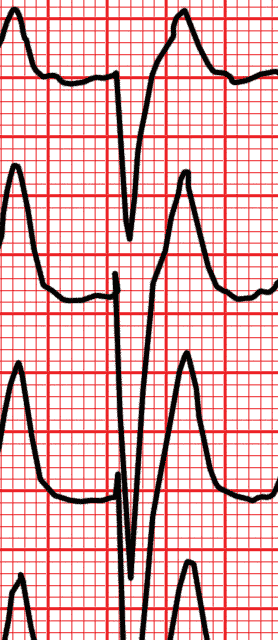

EKG Kurs

Obwohl eine der ältesten diagnostischen Tests aus dem späten 19. Jahrhundert, bleibt das EKG von entscheidender klinischen Nutzen. Diese Prüfung oft stellt immer noch Probleme bei der Auslegung für den Praktiker.

Dieser Kurs zielt darauf ab, den Studenten, Praktiker und sogar den erfahrenen Kardiologen Wissen in der Elektrokardiographie zu helfen. Es umfasst 250 Stellplätze unterschiedlicher Komplexität zusammen mit einer Beschreibung jedes einzelnen von ihnen durch Experten. Dies ermöglicht es dem Leser seine Analyse mit der von den Experten zu vergleichen. Weitere interessante Bereiche des EKG werden gut demonstriert aktiviert werden.